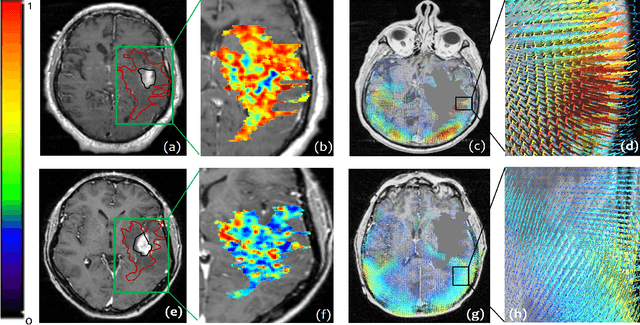

Abstract:The concept of tumor field effect implies that cancer is a systemic disease with its impact way beyond the visible tumor confines. For instance, in Glioblastoma (GBM), an aggressive brain tumor, the increase in intracranial pressure due to tumor burden often leads to brain herniation and poor outcomes. Our work is based on the rationale that highly aggressive tumors tend to grow uncontrollably, leading to pronounced biomechanical tissue deformations in the normal parenchyma, which when combined with local morphological differences in the tumor confines on MRI scans, will comprehensively capture tumor field effect. Specifically, we present an integrated MRI-based descriptor, radiomic-Deformation and Textural Heterogeneity (r-DepTH). This descriptor comprises measurements of the subtle perturbations in tissue deformations throughout the surrounding normal parenchyma due to mass effect. This involves non-rigidly aligning the patients MRI scans to a healthy atlas via diffeomorphic registration. The resulting inverse mapping is used to obtain the deformation field magnitudes in the normal parenchyma. These measurements are then combined with a 3D texture descriptor, Co-occurrence of Local Anisotropic Gradient Orientations (COLLAGE), which captures the morphological heterogeneity within the tumor confines, on MRI scans. R-DepTH, on N = 207 GBM cases (training set (St) = 128, testing set (Sv) = 79), demonstrated improved prognosis of overall survival by categorizing patients into low- (prolonged survival) and high-risk (poor survival) groups (on St, p-value = 0.0000035, and on Sv, p-value = 0.0024). R-DepTH descriptor may serve as a comprehensive MRI-based prognostic marker of disease aggressiveness and survival in solid tumors.